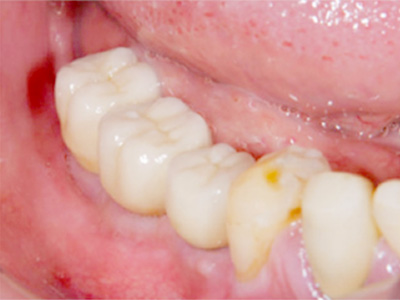

インプラント埋入術後、インプラントが骨に生着したので二次手術を行った後の写真です。

骨吸収の大きかった部位に、きっちり3本のインプラントが植立できました。 -

上部構造が完成した時の写真です。

見た目もきれいで、何でも食べられるようになっていただけました。